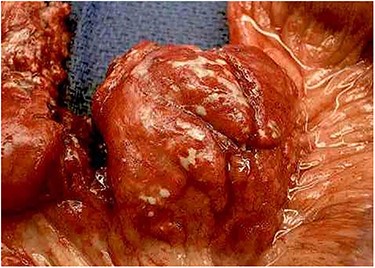

The entire excised specimen showing all of the enlarged necrotic lymph nodes and ischemic bowel.

Emergent laparotomy was performed. He was found to have multiple enlarged necrotic mesenteric lymph nodes with purulent material draining from the capsule of the nodes (Fig. 2). Several large areas of the proximal mesenteric fat were necrotic with vascular occlusion and thrombosis, which was causing ischemia of the proximal jejunum. The proximal jejunum was very dusky and dilated, while the distal small bowel and colon was normal. The duodenum was spared. The necrotic fat and lymph nodes extended down to and around the superior mesenteric artery, where multiple side branches off the artery showed no blood flow by Doppler examination. The ischemic small bowel was excised along with its mesentery down to the superior mesenteric artery, to include the excision of the necrotic lymph nodes (Fig. 3). The bowel was left in discontinuity, and the patient was taken to the intensive care unit with a temporary abdominal closure. He was taken back to the operating theatre the next day for a second look, and the remaining small bowel was found to be viable and healthy. A duodenal to distal jejunal anastomosis was performed and the abdomen was closed.